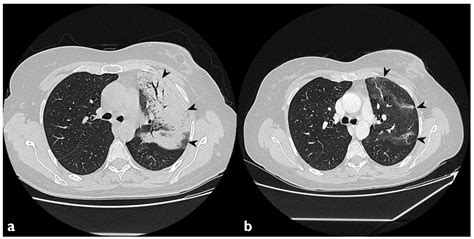

Once the scan is completed, a radiologist will interpret the images and generate a report. When viewing a Pneumonia CT Scan, medical professionals look for specific patterns of lung involvement. These patterns often indicate the type of pneumonia or the severity of the inflammatory response.

Common findings often described in reports include:

• Consolidation: This refers to the filling of air spaces (alveoli) with fluid, pus, or other material, appearing as dense, white areas on the scan.

• Ground-Glass Opacity (GGO): A hazy appearance in the lungs, indicating partial filling of air spaces or thickening of the lung interstitium. This is often seen in viral pneumonias.

• Pleural Effusion: The buildup of fluid in the space between the lung and the chest wall.

It is important to remember that these findings must always be correlated with the patient's symptoms, laboratory results, and clinical history. A report with "positive findings" does not always imply a worst-case scenario, as many patterns are typical of common bacterial or viral infections.